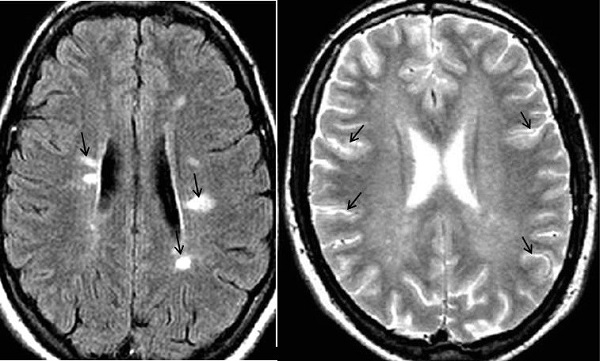

Diagnóstico por Neuroimagen:

La TC es poco sensible y normalmente no muestra ninguna alteración. La RM es la técnica más sensible y específica en la identificación de lesiones desmielinizantes del SNC, principalmente en EM, y es más específica cuando se contrasta con gadolinio62; en las secuencias T2 con ganodilio se evidencia hiperintensidad en todo el tejido cerebral, que refleja una ruptura inflamatoria de la barrera hematoencefálica y aumento tisular del agua libre. Las lesiones iniciales usualmente aparecen como nódulos de tamaño menor a 25 mm, la cuales pueden evolucionar a formas en anillo o de arco y se localizan principalmente en tejido parenquimatoso cerebral con una distribución perivascular; estas lesiones pueden confluir, formando placas hiperintensas con bordes irregulares, con forma característica en sierra (35%). Se localizan con mayor frecuencia en sustancia blanca periventricular (60%), cuerpo calloso (25%), sustancia blanca yuxtacortical y parénquima infratentorial (15%) 61,65.